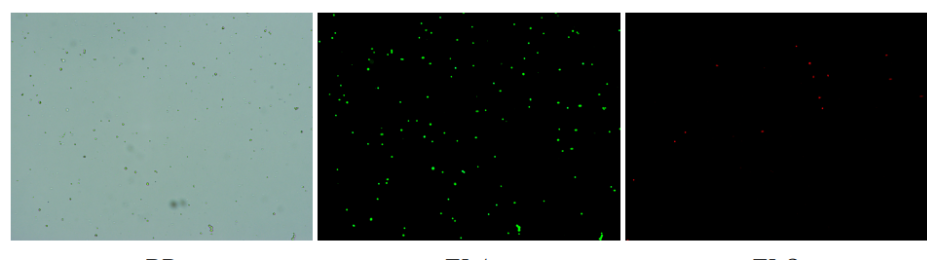

肝臟是人體代謝和解讀的器官,在體內發(fā)揮氧化、儲存肝糖、合成分泌性蛋白合成等,肝臟也制造消化系統中之膽汁,人肝約有25億個(gè)肝細胞。但是解離肝臟組織懸液并不簡(jiǎn)單,首先,肝臟代謝旺盛,離體后肝細胞無(wú)法進(jìn)行正常的有氧糖酵解,細胞活力會(huì )迅速下降,另外,肝細胞的線(xiàn)粒體很多,每個(gè)細胞大約有1000個(gè)左右,遍布于胞質(zhì)內。因此,很難得到符合單細胞測序要求的單細胞懸液。百邁客生物在肝臟組織單細胞懸液制備方面有豐度的實(shí)操經(jīng)驗,開(kāi)發(fā)了獨有的解離體系,下面來(lái)看實(shí)驗結果:

實(shí)驗結果

人肝癌樣本,懸液背景干凈,活性91.69%,結團率6%

人膽管癌樣本,活性90.45%,結團率7.2%

Tips: 肝實(shí)質(zhì)細胞經(jīng)過(guò)解離后因為缺氧非常容易發(fā)生凋亡,導致占比很低,如果老師關(guān)注肝實(shí)質(zhì)細胞的話(huà),建議采用單細胞核懸液的方法。